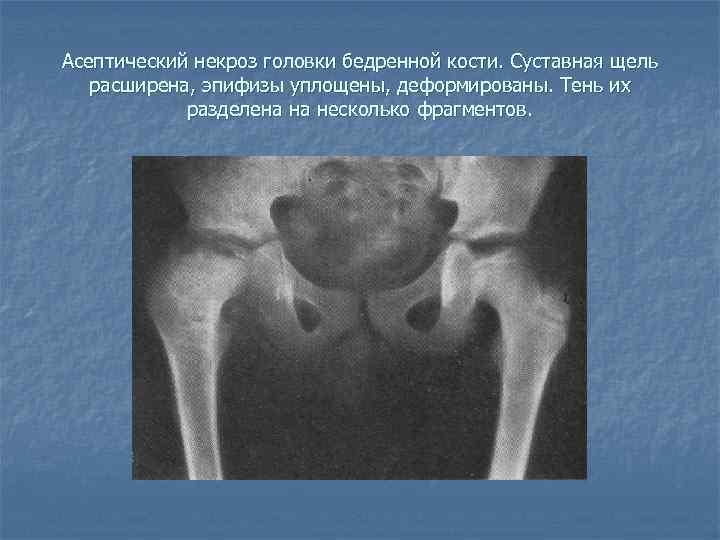

Некроз тазобедренного сустава: Фотографии и особенности лечения